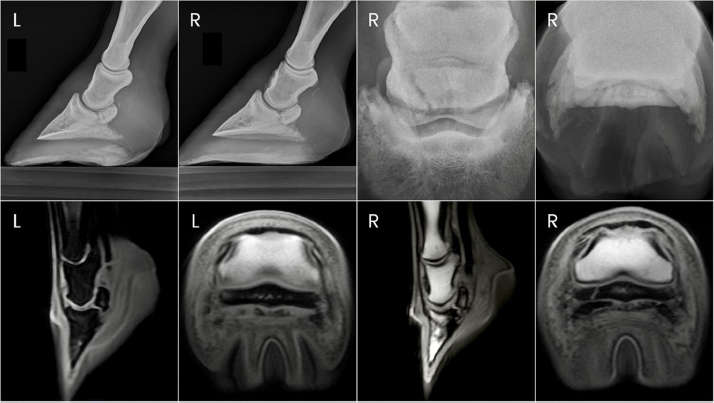

Fig. 3. Antemortem radiographs and postmortem MRI images of horse one showing bilateral navicular bone fractures, DIPJ hyperextension, and DDF tendon compromise.

Horse 1 remained pasture sound until day 84 post-PDN when he was presented for an abnormal gait with both toes displaying a mild dorsal elevation off the ground when weight bearing. Radiographs of the digits revealed parasagittal fractures of both forelimb navicular bones with hyperextension of both DIPJs (Fig. 3). Severe fiber pattern disruption of the DDF tendon was noted on ultrasound of both forelimb palmar pastern regions suggestive of severe DDF tendinopathy or rupture. Humane euthanasia was elected due to the severity of the pathology and poor prognosis. Postmortem magnetic resonance imaging (MRI) was performed on the forelimbs, which identified marked navicular bone degeneration with obliquely oriented, complete fractures of the lateral quarter of the navicular bone bilaterally, complete rupture of the DDF tendon extending from the distal aspect of the first phalanx to the navicular bone in the right forelimb, and nearly complete rupture of the DDF tendon in the left forelimb (Fig. 3). Additional findings of note in both forelimbs were hyperextension of the DIPJ, significant navicular bursitis with probable bursal adhesions, and desmitis of the impar, collateral sesamoidean, and distal digital annular ligaments.

Fig. 4. Ante-mortem radiographs and postmortem MRI images of horse two showing the right forelimb navicular bone fracture and bilateral DDF tendon compromise.

Horse 2 remained comfortable postoperatively with no appreciable lameness until approximately day 129, at which time a mild and inconsistent grade 4/5 RF lameness was noted. On day 136 post-PDN, the gelding was presented for student teaching of radiographic techniques. Radiographs were taken of both front digits, which revealed a parasagittal fracture of the right forelimb navicular bone and mild hyperextension of the right DIPJ (Fig. 4). Ultrasound revealed severe fiber pattern disruption of the DDF tendon suggestive of severe tendinopathy or rupture in the distal pastern region of both the right and left forelimbs. Humane euthanasia was elected due to the severity of the pathology and poor prognosis. Postmortem MRI was performed on both forelimbs revealing marked bilateral navicular bone degeneration with an obliquely oriented complete fracture of the lateral quarter of the navicular bone on the right forelimb, and bilateral severe DDF tendinopathy with almost complete rupture of the DDF tendon at the level of the navicular bone (Fig. 4). Additional findings of note in both forelimbs were significant navicular bursitis with probable bursal adhesions, enthesopathy of the flexor surface of the third phalanx at the DDF tendon insertion site, and impar, collateral sesamoidean ligament, and distal digital annular ligament desmopathy.